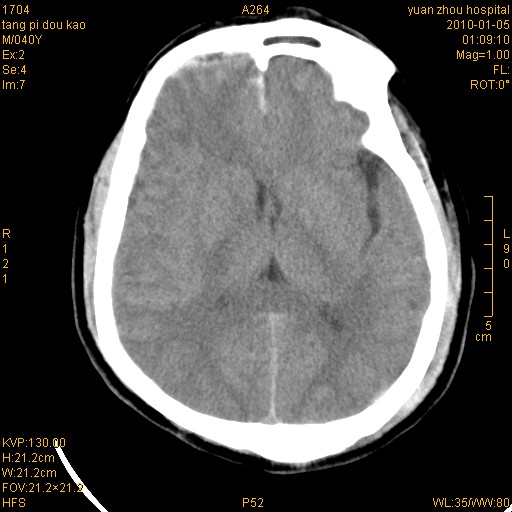

标题: CT23986:M 40Y 外伤数小时

双侧额叶 右侧大脑脚区多发血肿伴蛛网膜下腔出血!

1)左侧颞枕部硬膜外血肿。2)右侧额部硬膜下血肿。3)双侧额叶及右侧基底节下部脑挫裂伤。4)蛛网膜下腔出血。5)脑水肿。6)左侧前组筛窦及左侧额窦炎症。

前纵裂池的出血是硬膜下还是蛛网膜下腔?右额叶深区血肿还是基底节血肿?